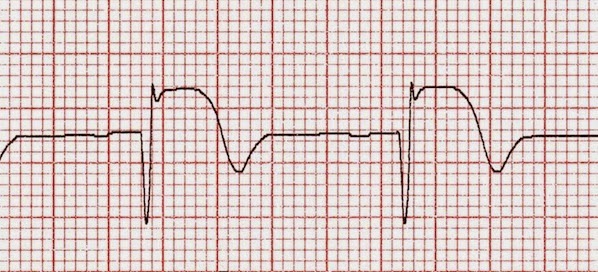

Am J Med, junio de 2018 Este metanálisis confirma la falta de beneficio de la oxigenoterapia de rutina en pacientes con infarto agudo de miocardio con niveles normales de saturación de oxígeno.